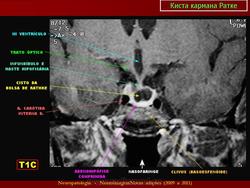

ГМ. Киста кармана Ратке. +

Киста кармана Ратке

Отличные изображения, спасибо. И хорошо что тут стрелочками указана киста и аденогипофиз, который всегда деформирован кистой и киста непосредственно к нему прилижет.

Ратке карман (sacculus hypophysialis; М. Н. Rathke, нем. анатом). Выпячивание эпителия задней стенки ротовой полости зародыша на границе с глоткой; зачаток аденогипофиза. Синоним: гипофизарный карман.